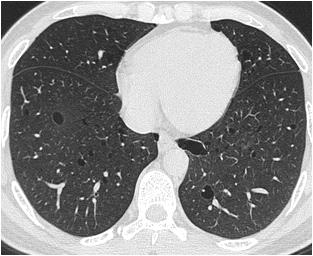

Hypophysitis was diagnosed based on the radiological score proposed by Gutenberg et. al. that showed a sensitivity of 92%, a specificity of 99%, a positive predictive value of 97%, and a negative predictive value of 97% for the diagnosis of autoimmune hypophysitis11. All such patients underwent routine cerebrospinal fluid (CSF) analysis, and estimation of adenosine deaminase (ADA), angiotensin-converting enzyme (ACE), β -human chorionic gonadotropin (hCG) and α-fetoprotein (AFP) in CSF in addition to measurement of serum immunoglobulin G4 (IgG4) level. Idiopathic intracranial hypertension (IIH) was suspected in presence of empty sella (ES), dilated optic nerve sheaths, protrusion of optic nerve papilla into the posterior globes, and compressed ventricles and CSF cisterns on MRI 12

Idiopathic intra-cranial Partial empty sella with protruded hypertension (n=1) optic nerve head inside orbit and dilated optic nerve